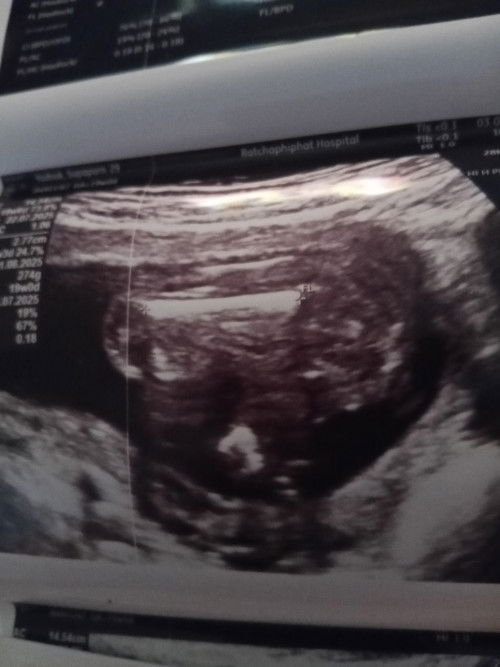

แบบนี้ ญ หรือ ช ค่ะพี่ๆ

เป็นกรีบเลยนะลูก🥰

ผู้หญิงค่ะ ชัดเจน

ลูกสาวค่ะ

Female ผู้หญิงค่ะ

ใช่คะ หมอบอกผู้หญิง แต่่อยากรู้ในรูป มีสิทธิ์จะเป็นผู้ชายมั้ยงับ ต้องทำหมันเเล้ว🤣